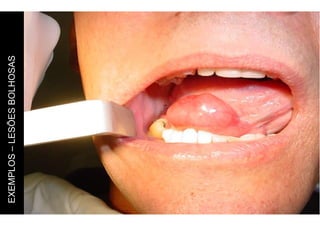

EXEMPLOS

–

LESÕES

VESICO-BOLHOSAS

Lesão de maior tamanho (mais do que 5mm).

Pode ser superficial ou profunda.

BOLHOSAS

Ao toque (palpação) percebe-se que o

conteúdo é líquido.